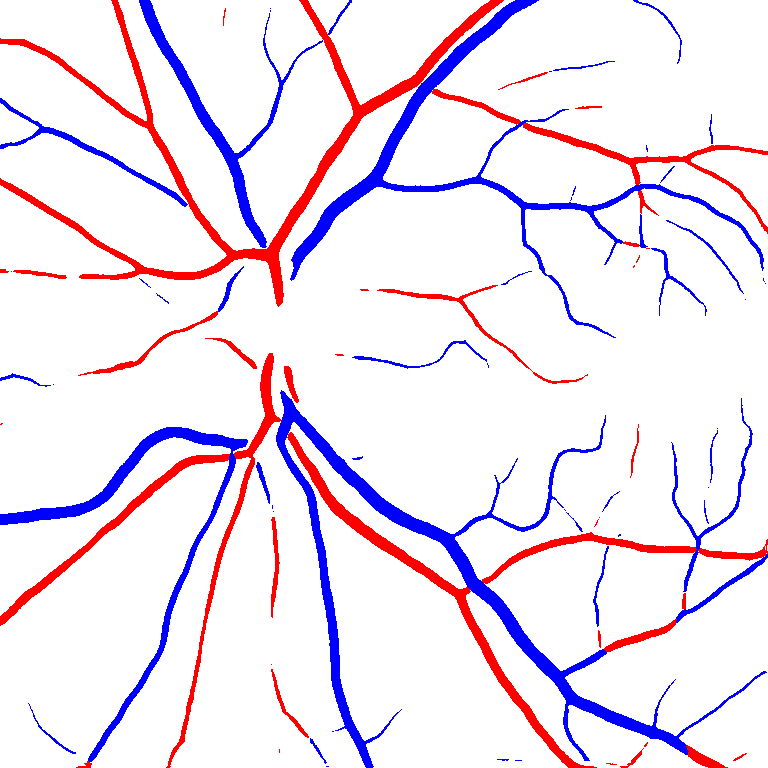

As reported in Table IV, we compared the SegRAVIR model against competing deep learning-based segmentation approaches on the RAVIR dataset. Evidently, SegRAVIR outperforms these methods as judged by all metrics for artery and vein classes with a healthy margin. In terms of Dice score, SegRAVIR outperforms CE-NET, IterNet and AG-Net by , and for artery segmentation and by , and for vein segmentation, respectively. Fig. 4 presents a qualitative comparison of the semantic segmentation outputs of SegRAVIR, CE-Net, and U-Net. Specifically, SegRAVIR yields more accurate vessel topology (i.e., thickness and orientation) segmentation with higher pixel-wise classification accuracy.

(a) (b) (c) (d) (e) (f)